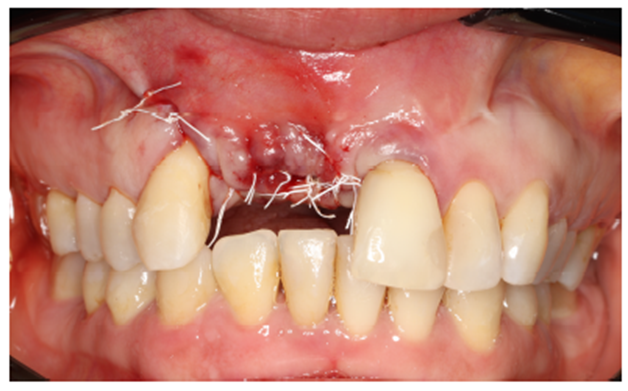

Um dos passos mais importantes dentro da cirurgia de reconstrução maxilar é o fechamento completo da ferida cirúrgica por primeira intenção. Deve-se evitar a qualquer custo a exposição do material de enxerto, pois o mesmo aumenta o risco de infecções. Antes do fechamento completo dos tecidos, é necessário remover quaisquer pontas ativas da membrana, deixando-a com as bordas arredondadas. Com o ganho expressivo do volume ósseo, a escarificação do periósteo é necessária para o relaxamento do tecido, evitando que o mesmo fique tensionado, diminuindo o risco de deiscência de sutura (Figura 9).

Após o preparo do tecido mole, foram colocadas membranas de L-PRF sobre as membranas de PTFE-d com o intuito de auxílio na reepitelização da cicatrização cirúrgica.

A escolha do fio é de extrema importância para o sucesso da cirurgia. Foi utilizado o fio de sutura de PTFE Cytoplast, cuja elasticidade acompanha o edema pós-operatório, diminuindo o risco de deiscência de sutura (Figuras 10 e 11).